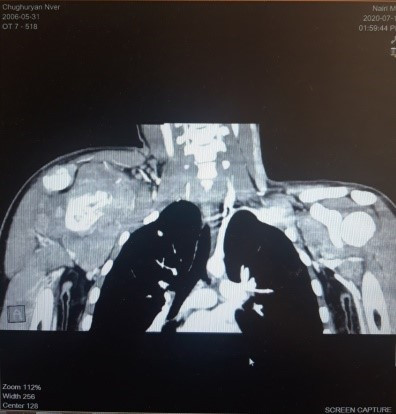

Նկար 1․ Թիակի ռադիոլոգիական պատկերը